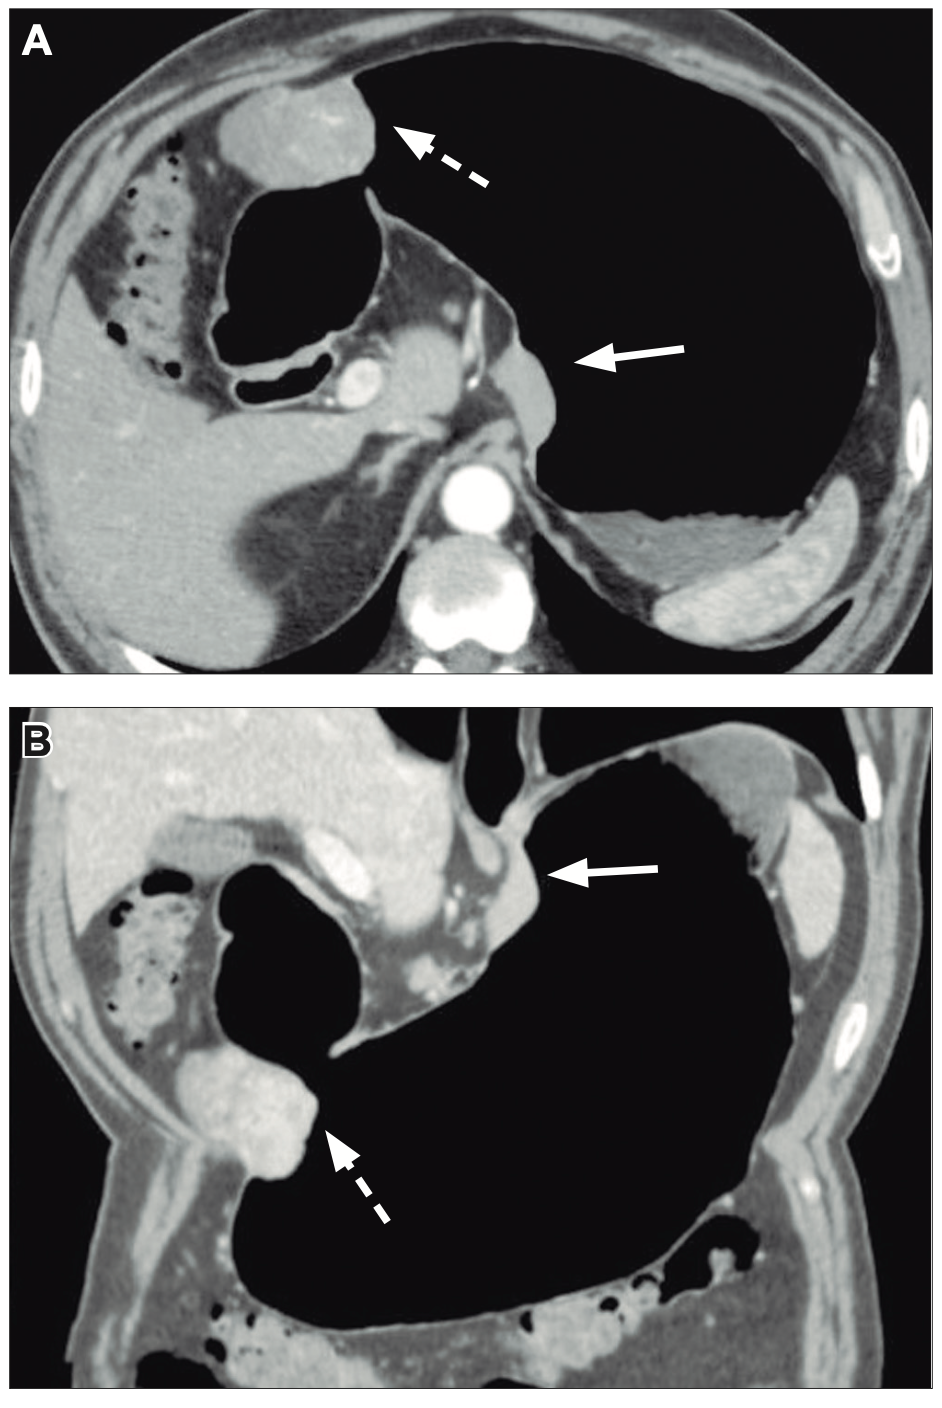

La tomografía computada prequirúrgica evidenció una masa subcardial con crecimiento hacia la luz y realce homogéneo tras la administración de contraste, y otra masa en el cuerpo distal de crecimiento mixto y realce heterogéneo (Figuras 1A y 1B). La reconstrucción tridimensional, similar a un estudio baritado del estómago, facilitó la localización precisa de ambos tumores (Figura 2). La endoscopía virtual proporcionó una visión intraluminal de ambas lesiones; mostrando la mucosa gástrica preservada (Figura 3). No se evidenciaron adenopatías regionales ni metástasis a distancia.

Figura 1. A y B